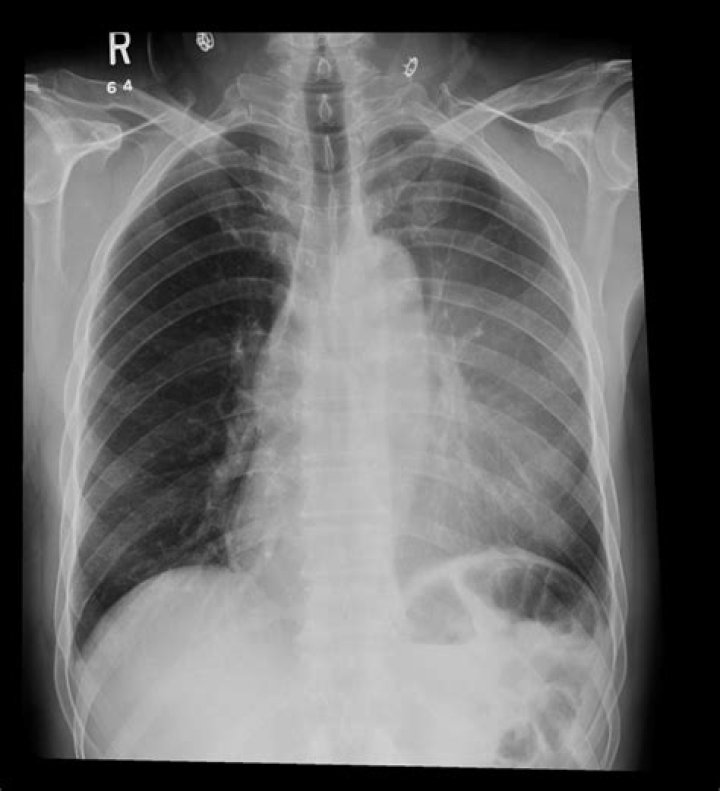

What does atelectasis mean on chest xray

What does atelectasis look like on CT?

Definition of Atelectasis: On x-rays and CT scans, reduced volume is seen, accompanied by increased opacity (chest radiograph) or attenuation (CT scan) in the affected part of the lung. Atelectasis is often associated with abnormal displacement of fissures, bronchi, vessels, diaphragm, heart, or mediastinum.